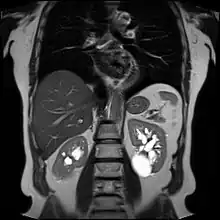

![]() | |

| Renal cyst of the left kidney (hyperintense area) as shown on MRI. | |

A renal cyst is a fluid collection in or on the kidney. There are several types based on the Bosniak classification. The majority are benign, simple cysts that can be monitored and not intervened upon. However, some are cancerous or are suspicious for cancer and are commonly removed in a surgical procedure called nephrectomy.

Numerous renal cysts are seen in the cystic kidney diseases, which include polycystic kidney disease and medullary sponge kidney.